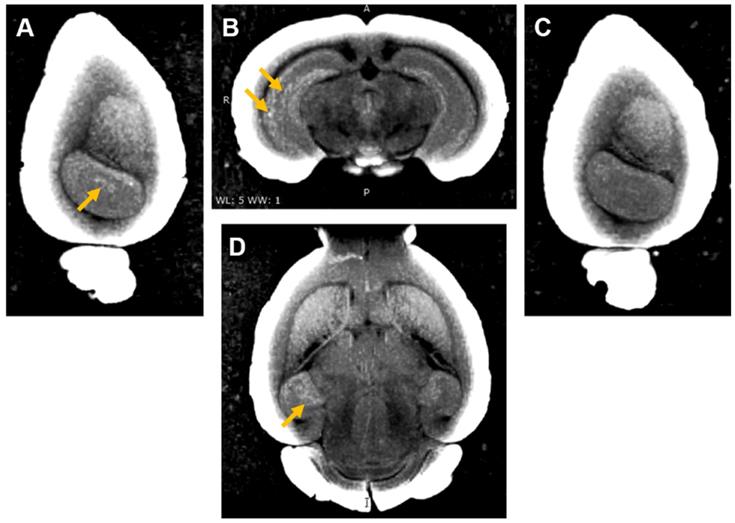

Three of the mouse brains where Gd(rhodamine-pip-DO3A) was delivered were then used to perform ex vivo MRI scans to check whether the probe could be detected by MRI as well as fluorescence microscopy. An increased brightness in T1 images was observed within the left hippocampus where the probe had been delivered (Figure 8 A, B, D). The amount of probe detected in the left hippocampus compared to the control right hippocampus was quantified with the normalized signal intensity, which showed a higher intensity detected in the left hippocampus compared to the control regions in all quantified images (Figure S6). After the MRI scans, the brains were sectioned to visualise the location of the fluorescence compared to that of the increased MRI contrast. Higher signal was detected in similar regions in both MRI (Figure 8) and fluorescence (Figure S7) images.

Figure 8

Ex vivo MRI images of brain with Gd(rhodamine-pip-DO3A) delivery to the left hemisphere. (A) Sagittal, (B) coronal and (D) axial MR views show enhanced T1 contrast in the left hippocampus compared to the (C) contralateral side. The localized distribution of the signal (arrows) confirms the targeted delivery of Gd(rhodamine-pip-DO3A). The periphery of the brain slices has a high intensity due to the increased contrast applied to the images to visualise the probe.